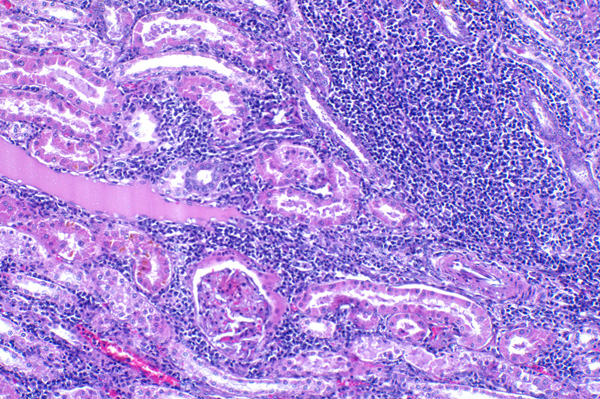

| 10x   |   Hematoxylin and Eosin | ||||

Extensive interstitial inflammation; ectatic tubule at left is filled with proteinaceous fluid.